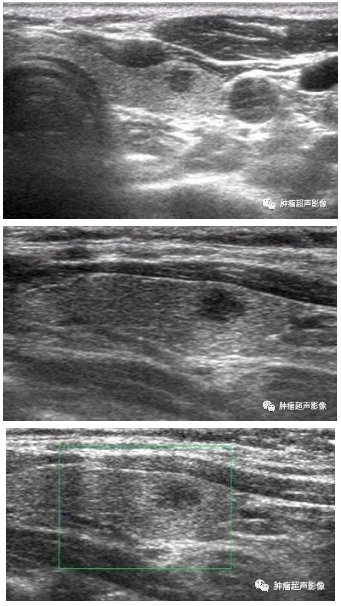

右侧颈部疼痛,右侧甲状腺肿大,形态不规则的低回声,边界模糊不清,回声不均匀,病灶回声从外向内逐渐降低,CDFI血流稀少;弹性成像显示质硬。

右侧甲状腺低回声,边缘不光整,回声不均匀, CDFI血流稍丰富。与甲状腺癌的鉴别超声并不好区分。

请继续看下面1个月、3个月后超声复查图像

男47,无压痛、无发热,甲状腺左叶低回声,边缘毛刺,无血流,国内某甲状腺顶级医院查左侧甲状腺低回声4类,与甲状腺乳头状癌不好鉴别,病理示肉芽肿性甲状腺炎。